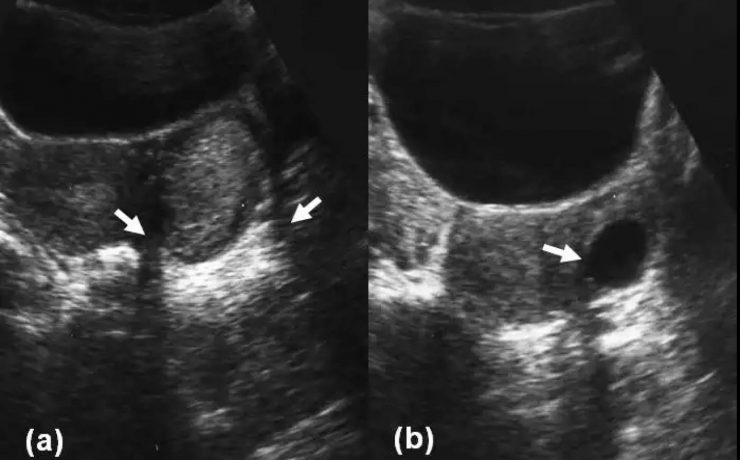

Este es un artículo de revisión publicado por el Departamento de Ginecología y Obstetricia del Hospital William Beaumont, Oaklahoma USA. La placenta accreta con sus variantes increta y percreta son una causa importante de hemorragia en el segundo y tercer trimestre de gestación representando hasta el 50% de las histerectomías